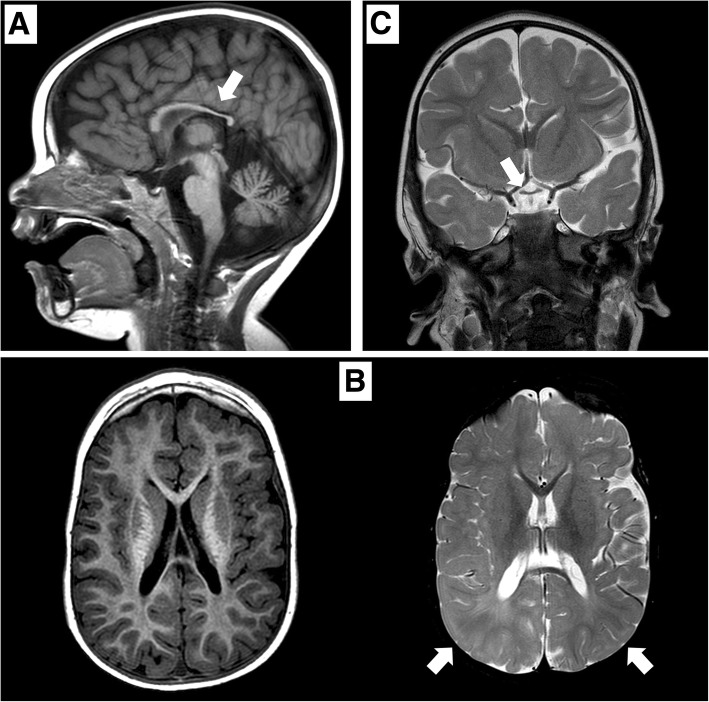

矢狀位 T1 加權(quán)圖像顯示胼胝體發(fā)育不全(白色箭頭)。 b 軸向 T1 加權(quán)(左)和軸向 T2 加權(quán)(右)圖像顯示胼胝體發(fā)育不全和雙側(cè)皮層下頂葉白質(zhì)(白色箭頭)中改變的、不明確的信號(hào)。 c 顯示視交叉發(fā)育不全的冠狀 T2 加權(quán)圖像(白色箭頭)

在 2 歲時(shí),患者無法保持目光接觸,也沒有發(fā)展語言技能。 直到 3 歲時(shí),他才能獨(dú)立坐下。此時(shí),頭顱 MRI 顯示雙側(cè)視神經(jīng)發(fā)育不全,并證實(shí)胼胝體發(fā)育不全(圖 (圖 1).1)。 為評(píng)估先天性心臟缺陷而進(jìn)行的超聲心動(dòng)圖顯示無阻塞的室間隔肥大。